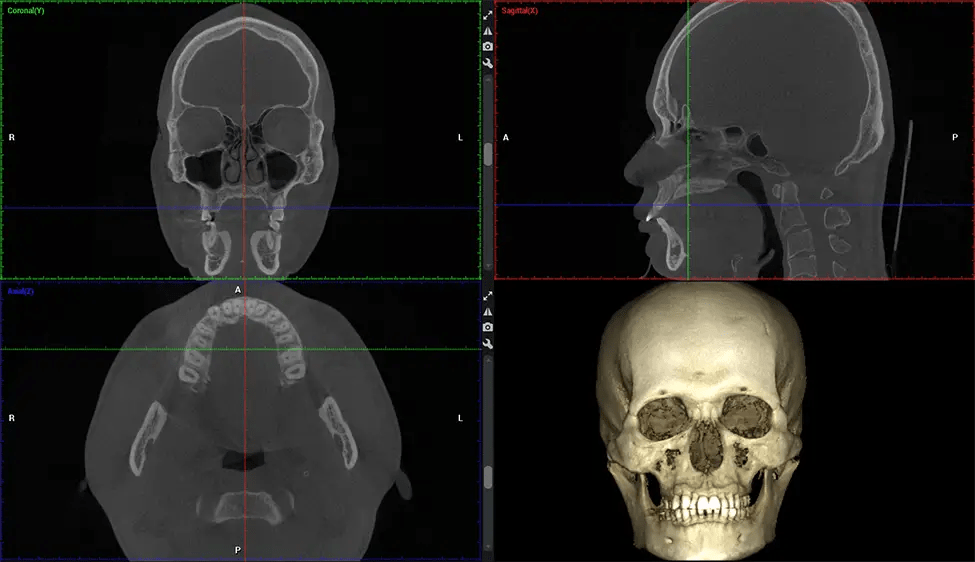

This 3D scan, called cone beam computed tomography, gives your dentist a more complete image of your oral anatomy and disease processes than a traditional X-ray. Unlike conventional X-rays, which capture a 2D image of your mouth from various angles, a 3D scan takes multiple digital X-rays for one image. It provides a complete view of your jaw, teeth, nerves, and soft tissues. This enhanced view allows dentists to detect minor issues not visible in traditional 2D scans, such as impacted wisdom teeth or bone fractures in the sinus cavity.

There are many benefits to using CBCT technology, especially compared to the traditional 2D X-ray format. One of the most significant advantages of CBCT scans is that they provide much more information than traditional X-rays. A scan lets your dentist see images from all angles of your jaw and mouth, including your sinuses, nasal cavity, cheekbones, and other surrounding areas. This added information helps your dentist craft a comprehensive treatment plan that addresses all aspects of your oral health.

Another significant benefit is that 3D imaging provides more precise images of your bone structure. These images are more detailed, providing you with a more accurate diagnosis. An accurate diagnosis means better treatment for you.

After the scanning process, the captured X-ray images are processed by the CBCT software, which applies algorithms to reconstruct a detailed 3D image of the scanned area. The software compiles these individual X-ray images and creates a digital 3D representation of the patient’s anatomy. The reconstructed 3D CBCT image can be viewed and analyzed by the dentist or radiologist. This image can be manipulated, rotated, and zoomed in or out to examine specific structures and evaluate the patient’s condition.